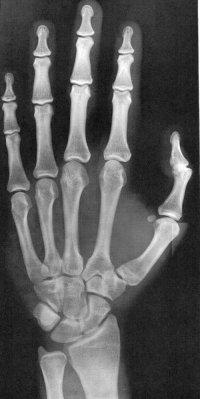

Sexo Masculino

5 anos